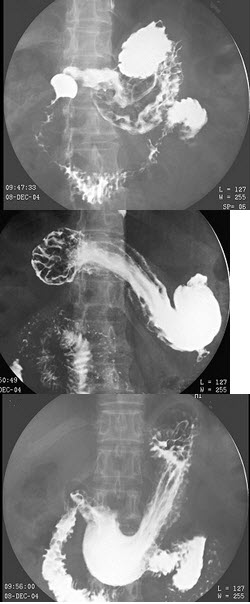

E.环形狭窄

85、多项选择题

男,12岁,上腹痛1周,无规律,无黑便史。体检:剑突下有压痛,结合图像,最可能的诊断是()

A.正常表现

B.胃炎

C.十二指肠炎

D.十二指肠溃疡

E.十二指肠占位

E.多处虫蛀状破坏

172、单项选择题

男,71岁,脾大、腹水、肝管结石2年,结合图像,最可能的诊断为()

B.会厌征

C.食管多发憩室

D.食管溃疡

E.食管癌